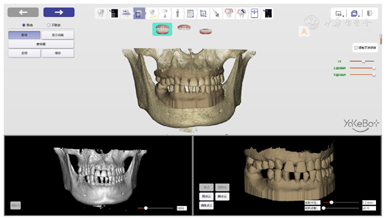

术前将颌骨数据和口内扫描数据导入自主式口腔种植机器人系统软件中,规划种植体位置、设计机器人种植步骤、设计机器人用手术配件;术中自主式口腔种植机器人在缺牙区微创植入两枚种植体;术后在机器人系统软件中评价种植精度。

在植体库中选择适合的植体,45牙为4.0 mm×11.0 mm柱型植体,46牙为5.0 mm×11.0 mm柱型植体,再根据牙冠穿出位点和骨量确定45、46牙种植体的位置(图8)。

根据种植体型号,规划机器人种植的下钻次序,在这一过程中,可以调整每一钻下钻的转速、起点、终点,同时要调整种植手机的姿态,避免种植手机柄部同邻牙发生碰撞同时避开软组织(图9)。

设计用于辅助机器人种植的手术配件,包括开口装置、视觉标记携带器、吸唾装置及注册孔等(图10)。